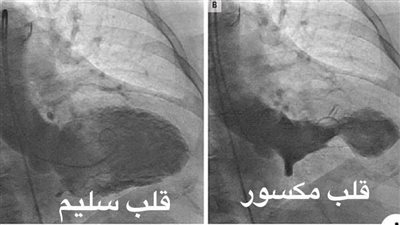

قلوب مكسورة

"متزعلوش".. دكتور يكشف خطورة القلب المكسور وينصح بعدم الحزن